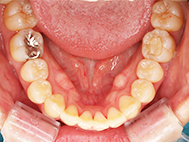

After

| 症状 | 上下前歯叢生 |

| 治療内容 | 上顎部分裏側矯正 下顎は目立ちにくい透明な装置 |

| 治療期間 | 11ヶ月 |

| 費用 | 620,000円 ※最新の治療費についてはご確認ください |

左上の前歯内側に入っている下の前歯ガチャ歯

左上前歯が下の歯の内側に入っているのが気になるとの事で来院されました。目立たない矯正治療を希望しているとのこでした。 上顎の装置は、歯の裏側(リンガル装置)で下顎は表側で矯正治療を行いました。口を閉じた時、上の前歯が内側に入っている為に下の歯を前に押し出している状態でした。その為、上の歯を前に出すだけではその歯が下とのかみ合わせの関係で、前に飛び出すような治療となってしまいます。 今回の症例ではシュミレーションを見て頂き、下の歯も治療し、内側へ下げることによって上の歯も飛びだすことなく、キレイにおさまることを説明し、上下一緒に矯正することをお勧めさせて頂きました。